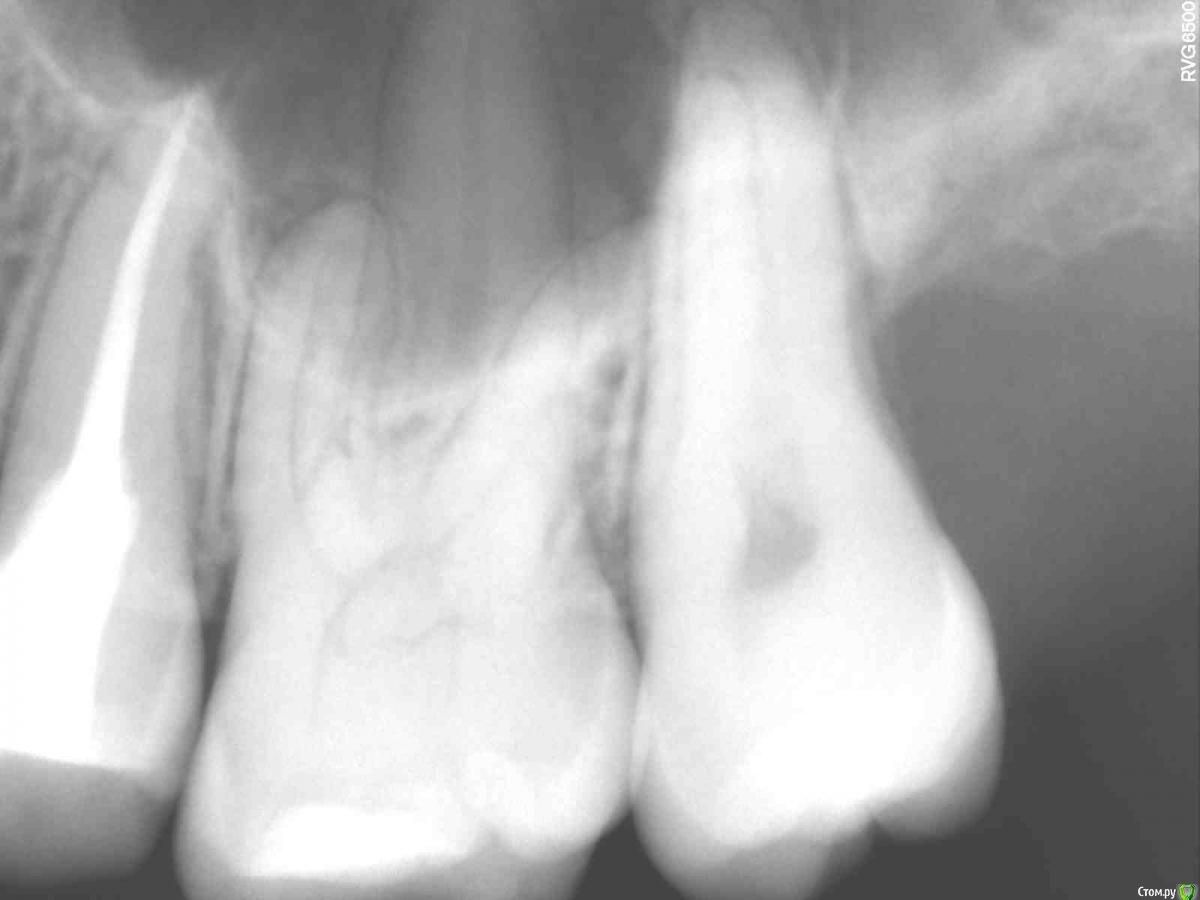

Алина08 Опубликовано 7 ноября, 2020 Поделиться Опубликовано 7 ноября, 2020 Добавлю ещё в эту тему. Здравствуйте, дорогие доктора, помогите пожалуйста,прилагаю панорам снимок. Слева были в феврале удалены мудрости, сверху вырезано,снизу вырван.Удаления были не сложные, но постоянно что-то мешало мне в ухе, а сейчас так вобще больно нажимать на челюсть снизу, болит челюсть, где 7 зуб и до подбородка. На кт было очень похоже на остаток корня рядом с корнем 7 зуба , но потом сказали это цвет кости такой другой. Сделала панораму и по мне так снизу явно видно, что там что-то есть. Как думаете? И что сверху слева у корня 7 зуба рядом?Мучают и боли лица, область пазухи и до глаза, там зубы 4 перелечили, 5 вывели материал сильно за корень , перелечили мта. Сейчас с 6 зуба достают пломбировочный материал, имеется аллергия на никель, в гутаперчи есть оксид никеля.Всё под микроскопом делалось, претензий к зубам нет у врачей, а боли начались как вскрыли 5 зуб, потом перелечили 4,не прошло, было ощущение распирания зубов, вскрыли 6 там дентикль, теперь его перелечивают, исключая аллерген контакт со слизистой, имею большие пазухи . Боль постоянная, распирающая, чувство давления на зубы. Может ли это боль снизу идти наверх? Выпито куча таблеток от невралгии, не помогает. Предлагают рвк 5 зуба, так как он на стук и кушать самый больной, у 6 зуба, если материал весь не достанут, осталось пару мм, тоже один корень верхушку убрать, но там пазуха рядом, не факт, что врач возмется. Придагалаю панораму и маленькие снимки 4,5,6 зубов.Больше меня сейчас волнует, есть ли кусок корня снизу от 8 зуба. Ссылка на комментарий

сирена Опубликовано 8 ноября, 2020 Поделиться Опубликовано 8 ноября, 2020 Нет там ничего внизу. Боли могут быть мышечные,когда удаляли зубы и потом лечили,приходилось долго держать открытым рот,мышцы "устали" и сейчас беспокоят такие неясные боли.Это называется миофасциальный болевой синдром.Вылечите шестой и сделайте перерыв в лечении.Пусть врач пропальпирует жевательные мышцы,если где-то будет болевой узел,то это оно.Резекций никаких не надо делать пока. Ссылка на комментарий

Алина08 Опубликовано 8 ноября, 2020 Автор Поделиться Опубликовано 8 ноября, 2020 (изменено) Спасибо, за ответ, Был период, когда 3 месяца ничего не делали, боли лица сохранялись, и зуб на стук больной с апреля и кушать на нем больно, 5 зуб, вот на нем и предлагают резекцию, прежде чем рвать, зуб подвижный, мышцы, суставы все щупали, проверяли, зубы удаляли в феврале, по моему много времени прошло, с момента травмы, когда боль сильная распирает зубы сверху, то визуально и место пазухи на лице припухает. Будет ещё обследование нервов на лице током и если там нервы не повреждены, то это точно зубы. Пока тоже думаю с 6 закончить, и отдохнуть, но ощущение, что виной всему 5 зуб с него все и началась ещё в апреле. Теперь и 7 снизу болит, у меня все зубы почти с дентиклями ещё, но это не показатель все вскрывать, 6 был с большим камнем, на воду чувствительность, вот и вскрыли, в 7 снизу тоже есть камни, и тоже стал чувствовать холод Нет там ничего внизу. Боли могут быть мышечные,когда удаляли зубы и потом лечили,приходилось долго держать открытым рот,мышцы "устали" и сейчас беспокоят такие неясные боли.Это называется миофасциальный болевой синдром.Вылечите шестой и сделайте перерыв в лечении.Пусть врач пропальпирует жевательные мышцы,если где-то будет болевой узел,то это оно.Резекций никаких не надо делать пока.Спасибо, за ответ, Был период, когда 3 месяца ничего не делали, боли лица сохранялись, и зуб на стук больной с апреля и кушать на нем больно, 5 зуб, вот на нем и предлагают резекцию, прежде чем рвать, зуб подвижный, мышцы, суставы все щупали, проверяли, зубы удаляли в феврале, по моему много времени прошло, с момента травмы, когда боль сильная распирает зубы сверху, то визуально и место пазухи на лице припухает. Будет ещё обследование нервов на лице током и если там нервы не повреждены, то это точно зубы. Пока тоже думаю с 6 закончить, и отдохнуть, но ощущение, что виной всему 5 зуб с него все и началась ещё в апреле. Теперь и 7 снизу болит, у меня все зубы почти с дентиклями ещё, но это не показатель все вскрывать, 6 был с большим камнем, на воду чувствительность, вот и вскрыли, в 7 снизу тоже есть камни, и тоже стал чувствовать холод. А чтобы мышцам отдохнуть, месяц 2 это мало? Или больше надо? Извиняюсь, не разобраться мне тут немного с сообщениями на форуме Изменено 8 ноября, 2020 пользователем Алина08 Ссылка на комментарий